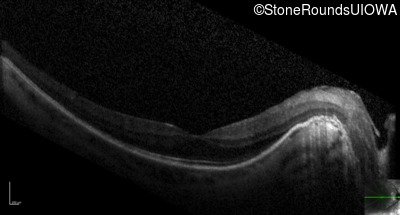

Optical Coherence Tomography - Right - 20/16 -2

Exemplar / OCT Stack